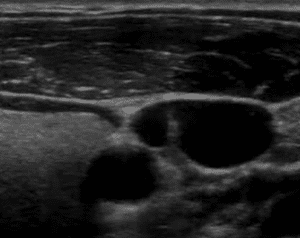

Punción con ecografía

Cuando se trata de una línea media es necesario usar un ecógrafo para poder visualizar las venas y proceder a la inserción, ya que los vasos de primera elección son profundos (vena basílica o vena cefálica).

6

La ecografía es muy utilizada y recomendada para todo tipo de vías centrales: reservorios, PICCS, centrales; así como para las líneas medias. Al hacer visible las venas y su recorrido, permite aumentar mucho la tasa de éxito en el primer intento (del 77% al 99%).

Además, el ecógrafo permite medir el calibre de las venas, lo que da la ventaja de elegir el diámetro adecuado del catéter respecto a la vena elegida. Cualquier catéter tiene que ocupar solo 1/3 de la luz de la vena.